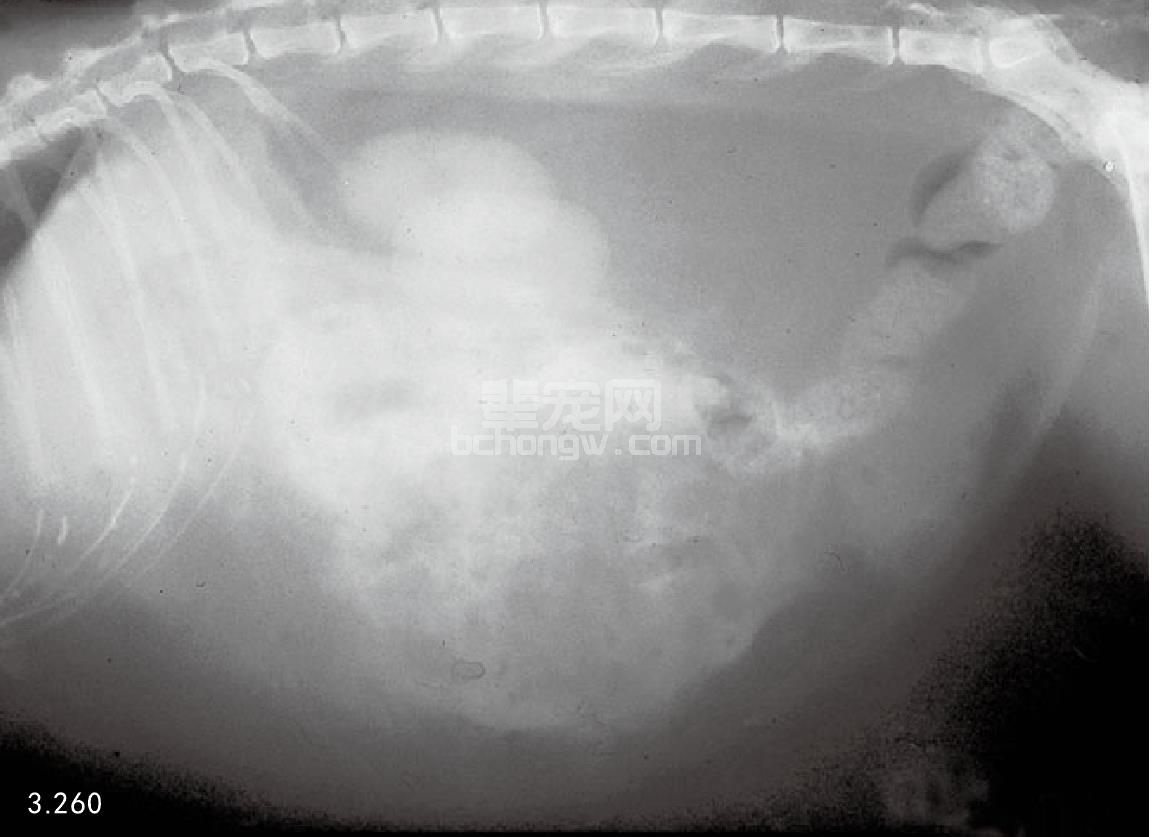

图3.260 图3.259中表现有急性胰腺炎猫的侧腹部X线片:显示有弥散的腹部渗漏液和小肠管的 “集合效应”。在外科手术中(图3.261)看到这些损伤是很明显的。大量的腹膜后腔脂肪导致了降结肠的腹侧下降。